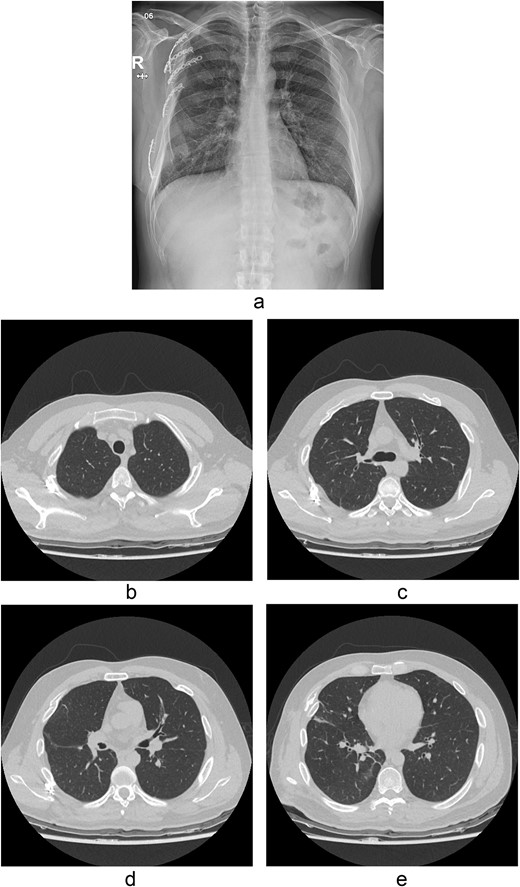

The thoracotomy incision was relatively small, ~8 cm in size, and the intercostal space was not spread to prevent further intraoperative chest wall damage. There were multiple lung lacerations in the upper, middle, and lower lobes with active bleeding. Bloody leakage continued through the avulsed parietal pleura and mediastinum. Hemostasis was achieved by suturing the deeply lacerated lung and packing with gauze (Combat Gauze ™ [Z-Medica QuikClot]) at the chest wall and mediastinum. The operation took 130 minutes. The transfusion of plasma, platelets, and red blood cells was balanced according to the following quantities: 10, 10, and 14 U, respectively. After surgery, the patient was transferred to the intensive care unit (ICU). The PaO2/FiO2 ratio was 52 mmHg with a Positive end expiratory pressure of 15 cm H2O, at a peak inspiration pressure of 30 cmH2O. ABGA showed pH 7.23, pCO2 42, and pO2 47. Veno-venous ECMO based on bilateral femoral vein cannulation was performed (Fig. 3a). Considering the patient’s hemorrhagic predisposition, heparin was not used. Disseminated intravascular coagulation (DIC) occurred along with acute renal failure. Antithrombin III infusion and continuous renal replacement therapy (CRRT) were initiated on the second hospital day. By the 5th day, oxygenation was achieved without ECMO support, followed by decannulation. On the 6th day, the second operation was performed in about 35 minutes. The gauze was removed, and no active bleeding or oozing was seen (Fig. 3b). The third operation, performed on the 13th day, was an open reduction of right ribs 3–7 for correction of flail chest and took 75 minutes (Fig. 3c). After open reduction, the flail chest improved, but the patient was not able to be weaned off the ventilator. Pneumonia and bacteremia developed. A tracheostomy was performed on the 15th day. CRRT was switched to hemodialysis, which was stopped on Day 28. The patient was discharged on the 47th day without tracheostomy. Ten months postoperatively, pulmonary function testing revealed forced expiratory volume in one second and diffusion capacity of carbon monoxide of 77% and 67% of predicted values, respectively. The chest CT and radiographs showed that the lungs had healed well, and there was no displacement of the ribs (Fig. 4). The patient recovered and returned to work.

Simple radiographs obtained after each operation. (a) Radiograph after the first operation. Gauze, which is visible as a wavy white line, was packed in the right thoracic cavity. Multifocal opacity was seen in the right lung, and there was left upper lung atelectasis. ECMO catheters were placed in the IVC. (b) Radiograph following the second operation. The right ribcage is narrowed due to displaced fractured ribs. (c) Radiograph after the third operation. Five plates were applied to the fractured ribs.